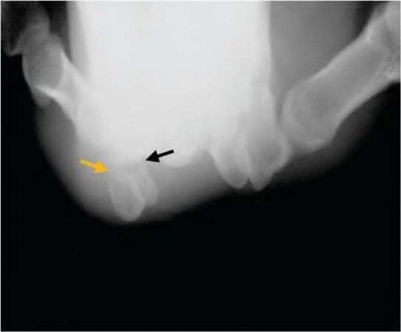

A 35-year-old woman reports wrist pain after a fall onto an outstretched hand. On exam, she has focal tenderness over the wrist snuffbox. A radiograph and CT image are shown in Figures A and B. What is the proper treatment of her injury?